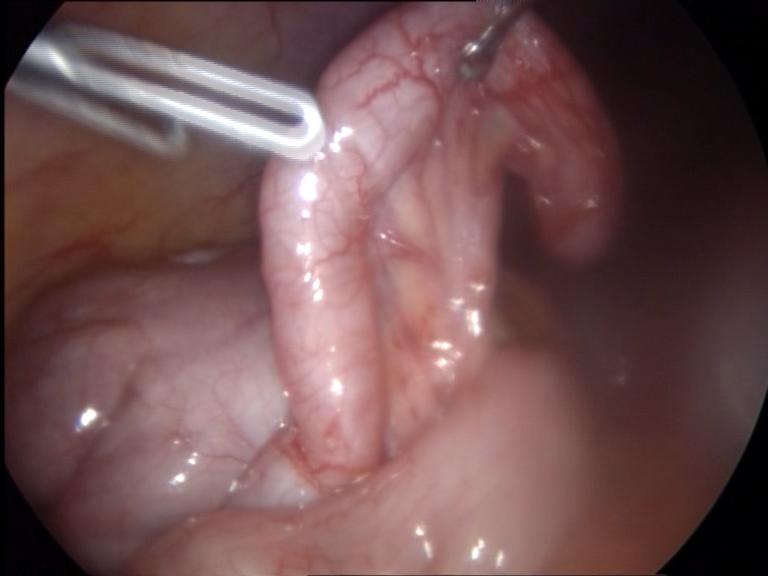

Εγκολεασμός

Εγκολεασμός καλείται η ενσφήνωση τμήματος του εντέρου στο κατά συνέχεια αμέσως επόμενό του, δηλαδή η αναδίπλωση του εντέρου μέσα στον ίδιο του τον αυλό. Μπορεί να συμβεί σε οποιαδήποτε ηλικία, όμως η μεγαλύτερη συχνότητα εμφανίζεται σε παιδιά ηλικίας 4-10 μηνών.